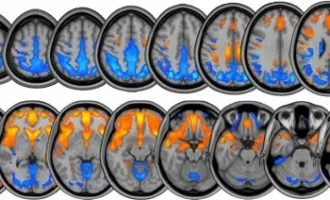

علمی ناسا در حال بررسی پیامدهای جاذبه صفر روی مغز انسان است

در جاذبه صفر، بالا و پایین معنا ندارد، در نتیجه آن قسمتی از مغز ما که کار محاسبه فضاهای سه بعدی را انجام می دهد در ...